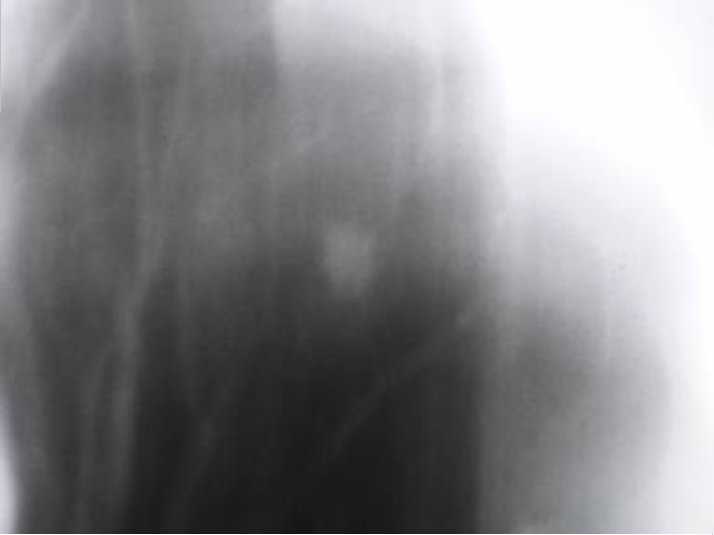

Протокол. На прямой цифровой флюорограмме органов грудной полости (1), произведенной в прямой стандартной проекции слева в 1 межреберье дифференцируется малоинтенсивная очаговоподобная тень. При цифровой обработке изображения (2) – эквилизация, увеличение в два раза, вышеописанная тень неправильной овальной формы, малой интенсивности с нечеткими контурами. На томограммах – оптимальный срез 11 см. (3, 4) на уровне 1 ребра определяется крупноочаговая тень размерами 1,0 х 0,8 см. средней интенсивности, почти однородной структуры с неровными, нечёткими контурами за счёт мелкой лучистости по контуру.

3. томограмма – оптимальный срез 11 см

4. томограмма – оптимальный срез 11 см.